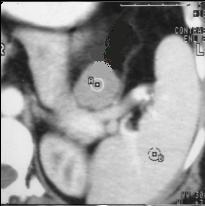

Lymphome gastrique :

Une epaississement diffuse a hypodense mais sans

stenose de l' estoma ( image TDM en coupe axiale ) .N'a

pas de rigidite a la region lesionaire |